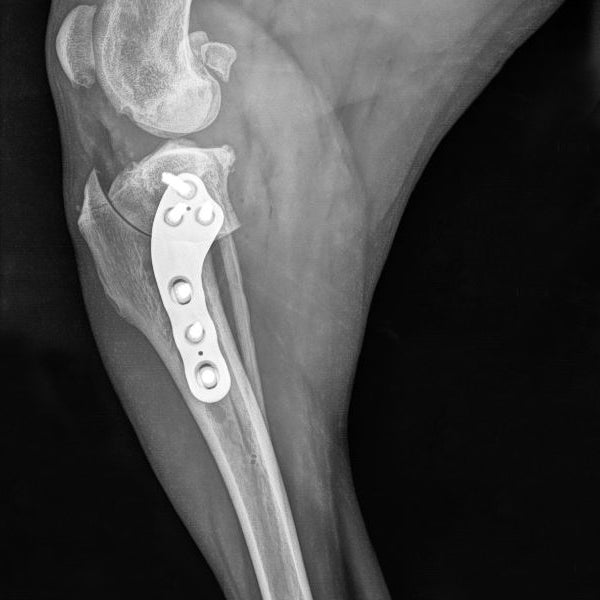

This course is designed for small animal practitioners seeking practical, effective methods to manage long bone fractures in dogs and cats. Participants will learn simplified techniques suitable for both straightforward and comminuted fractures, using modern implants that enhance surgical efficiency and reduce costs. By following key principles of fracture repair, complications can be minimized and outcomes improved.

Through a combination of lectures, clinical case discussions, and hands-on practice, attendees will gain confidence in choosing appropriate fixation methods and performing repairs. Practical sessions include fracture repair on plastic bone models and cadavers, followed by postoperative radiographs to assess technique and reinforce learning.

Apply the biomechanics of intramedullary pins, cerclage wires, bone screws, and plates, including compression, neutralization, and bridging methods